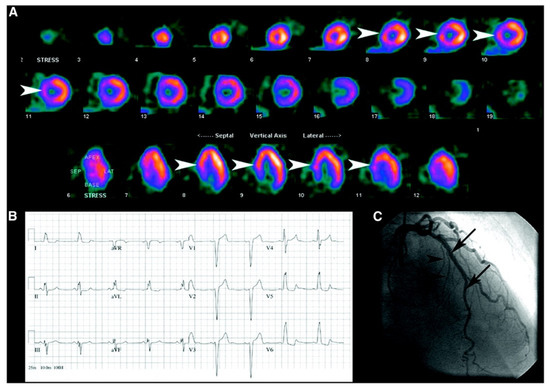

| Balanced ischemia | Balanced ischemia refers to a condition where there is an equal reduction in blood flow across all regions of the myocardium during stress. It is typically caused by factors including coronary artery disease, resulting in narrowed or blocked coronary arteries. SPECT imaging revealed a uniform decrease in radiotracer uptake throughout the myocardium, indicating impaired perfusion to the entire heart. | |